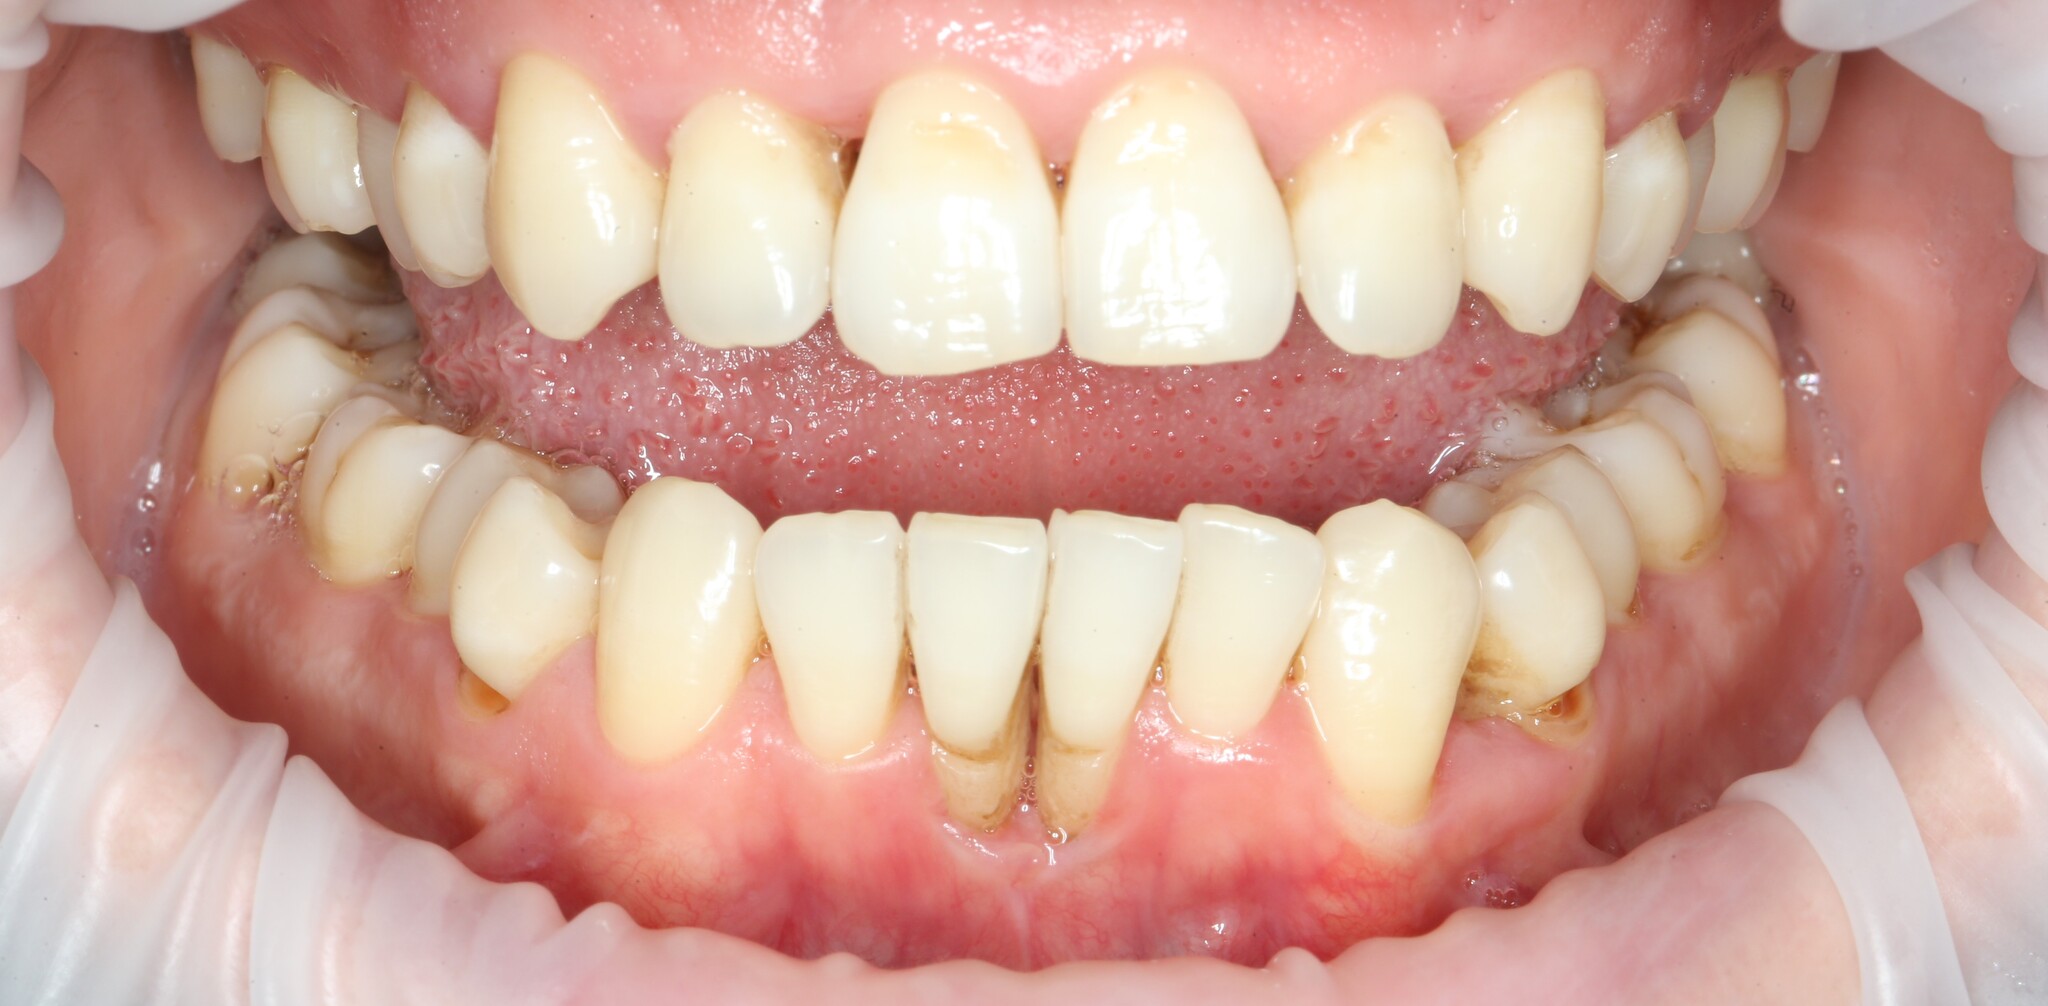

Чуть больше года назад в нашу (не побоюсь этого слова) уютную клинику на консультацию к ортодонту пришла девушка, возжелавшая исправить прикус и решить проблему рецессий десны в области нижних центральных зубов. Причина рецессий нумеро уно – это перегрузка зубов из-за неправильного их смыкания. Проще говоря, патологического прикуса. Поэтому нет вообще никакого смысла проводить закрытие рецессий без исправления прикуса. Деньги отдали, «эмоции» получили, а через какое-то время все снова стало так, как было (и это в лучшем случае).

Фотографии, сделанные на первичной консультации:

Ниже пунктиром отмечен переход подвижной слизистой в неподвижную. В некоторых местах, особенно в области центральных резцов прикрепленной десны, практически нет. В связи с чем образовались такие явные рецессии. Видно?